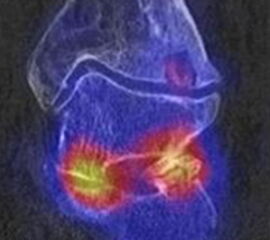

Abbildung 1.8.a und b: Akute Arthritis bei bekannter Gicht in beiden OSG: links die Früh-/Weichteilphase; rechts die Mineralisations­phase. Deutliche, entzündlich bedingte Mehranreicherungen in der Früh-/Weichteilphase. In der Mineralisation­sphase erkennt man die entzündliche Mitreaktion der subchondralen Gelenkabschnitte.

Abbildung 1.8.c - e: Akute Arthritis in beiden OSG, rechts > links. Im SPECT/CT erkennt man die Mitreaktion der subchondralen Gelenkabschnitte. Die Arthritis ist so akut, dass (noch) keine ossären morphologischen Veränderungen im CT abgrenzbar sind.